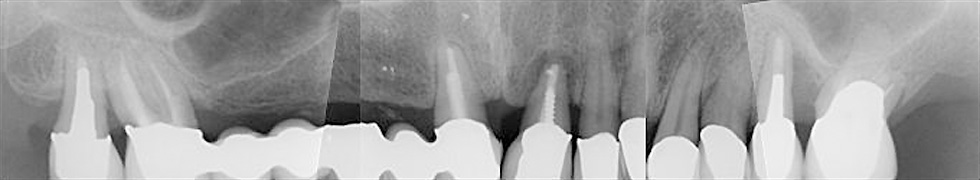

Abb. 1a: Röntgenstatus vom 14. Juli 2009

Abbildung 1: Radiologisch liegen folgende Diagnosen vor: Insuffiziente Wurzelfüllungen an 18,17,21,26, Beherdung an 21, zervikale Karies an 17,11, enge Wurzelproximität an 18,17, Tiefer intraalveolärer Knochendefekt an 25,26.